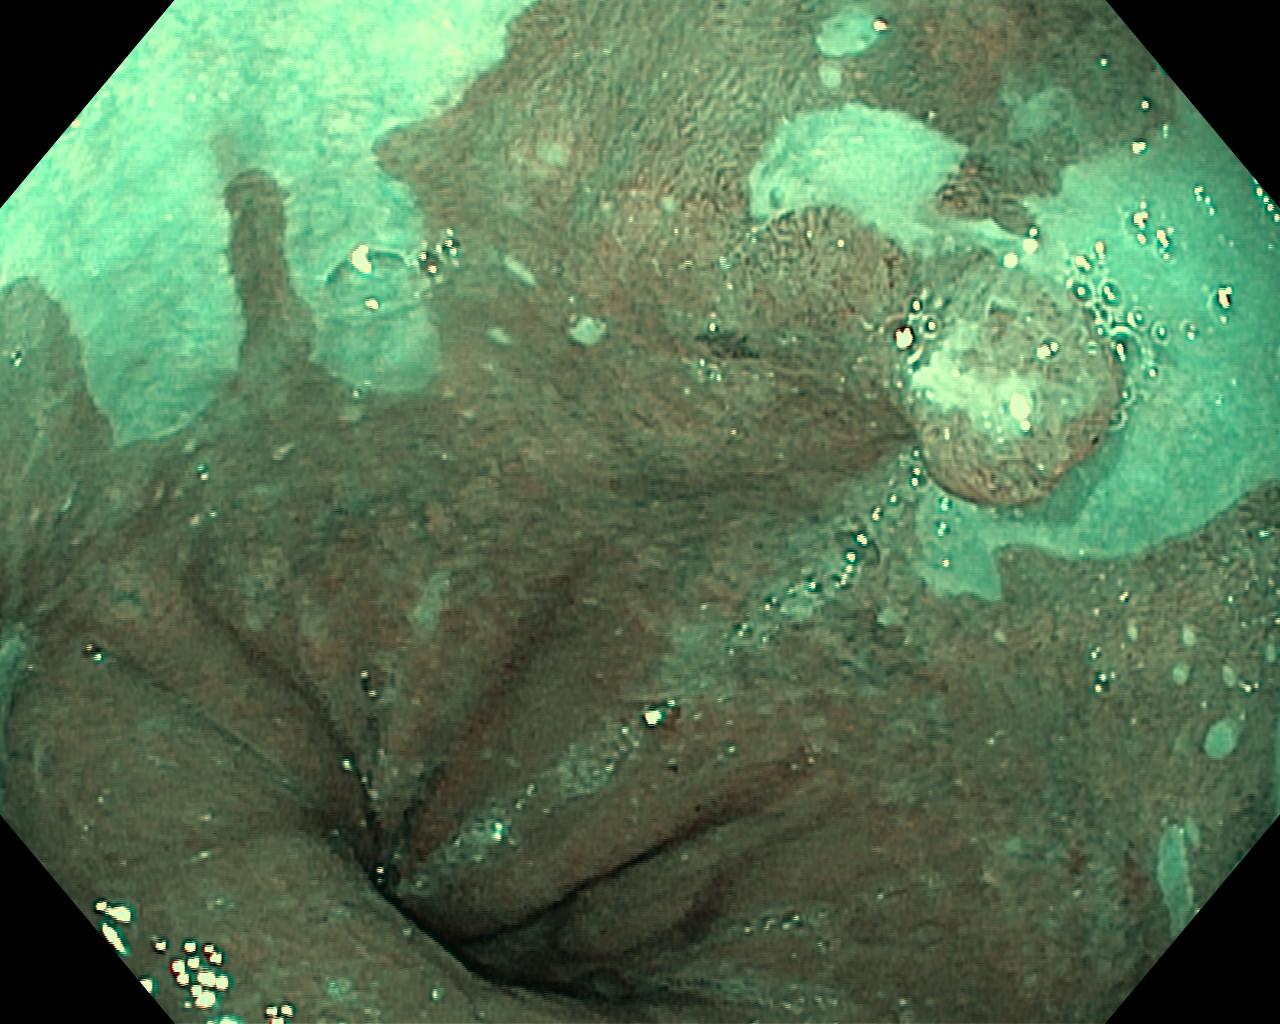

Przełyk Barretta